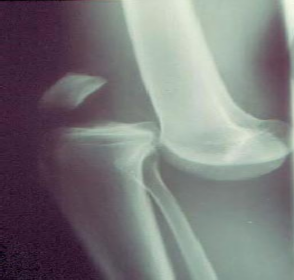

- Một số hình ảnh Xquang gãy xương, sai khớp cần lưu ý có tổn thương động mạch

Hình thái: gãy xương, sai khớp di lệch lớn, đầu xương gãy sắc nhọn hướng về phía động mạch (ảnh 1.2. và ảnh 1.3) gợi ý có nguy cơ chèn ép động mạch.

Ảnh 1.2: Hình ảnh Xquang gãy mâm chày ở BN đứt động mạch khoeo.

*Nguồn: theo Trịnh Vũ Nghĩa (2010)[19]

Ảnh 1.3: Hình ảnh Xquang sai khớp gối ở BN tổn thươngđộng mạch khoeo

⃰ Nguồn: theo Perron A.D., Brady W.J., Sing R.F. (2001)[86]

Vị trí: gãy 1/3 dưới xương đùi, gãy đầu dưới xương đùi, sai khớp gối hoặc gãy mâm chày có thể tổn thương động mạch khoeo.